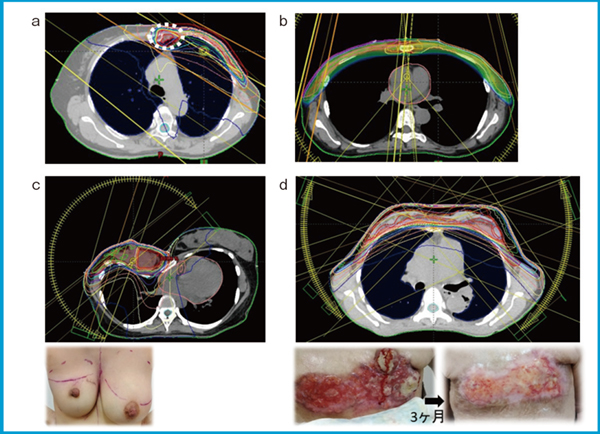

図1 VMATを用いたプランの一例

a:SIB-VMAT(IMNへのブースト)

b:両側IMNを含む乳房全切除後放射線治療(PMRT)

c:漏斗胸の患者,腫瘍床ブースト

d:両側に広がる局所進行乳がんへの照射

もう一つのVMATの利点は,同時ブースト(SIB)による高線量照射を治療期間の延長なく実施できる点である。実際,IMN転移に対し63.6〜70.4 Gyを投与した群は,低線量群より5年DFSが良好であったとの報告がある6)。筆者らは2018年より,IMNを含むRNIに「TrueBeam」や「Halcyon」(共にバリアン社製)を用いたSIB-VMATを導入し,CTで腫大を認める部位に対して56.25〜60 Gy/25回を投与している(図1 a)。初期33例の解析では,平均心臓線量3.7 Gy,肺V20:12.7%,V5:38.4%を達成し,Grade 2以上の肺臓炎は認められず,IMNを含む高リスクRNIをVMATで安全に実施しうることが示唆された7)。

VMATは,複雑な解剖学的条件や臨床状況においても有用である。例えば,両側IMNを含むRNIは,3D-CRTでは照射野の重複や肺線量の制約が課題であったが,VMATでは胸壁に沿うようビームを配置することで治療が可能となる(図1 b)。

また,漏斗胸など胸郭変形症例では,胸壁形状の不均一性により従来法では線量均一性の確保が困難であり,電子線ブーストも実施困難な場合がある。VMATを用いることで,乳房全体に均一な線量を与えつつ,腫瘍床にもブースト線量を効果的に加えることが可能となる(図1 c)。創傷治癒遅延や既往照射歴がある場合にも,VMATは線量を調整しながらRNIを安全に行う手段となる。

さらに,手術不能局所進行乳がんによる皮膚潰瘍や出血に対する緩和的放射線治療においては,SIB-VMATにより腫瘍中心部への高線量照射が可能であり,症状緩和やQOLの改善が期待される。筆者の施設では,両側乳がんの広範な腫瘍に対し,皮膚浸潤部に45 Gy,粗大腫瘍に52.5 GyのSIB-VMATで同時照射し,肺線量を良好に抑制しながら出血・滲出液の大幅な軽減と腫瘍縮小を得た(図1 d)。